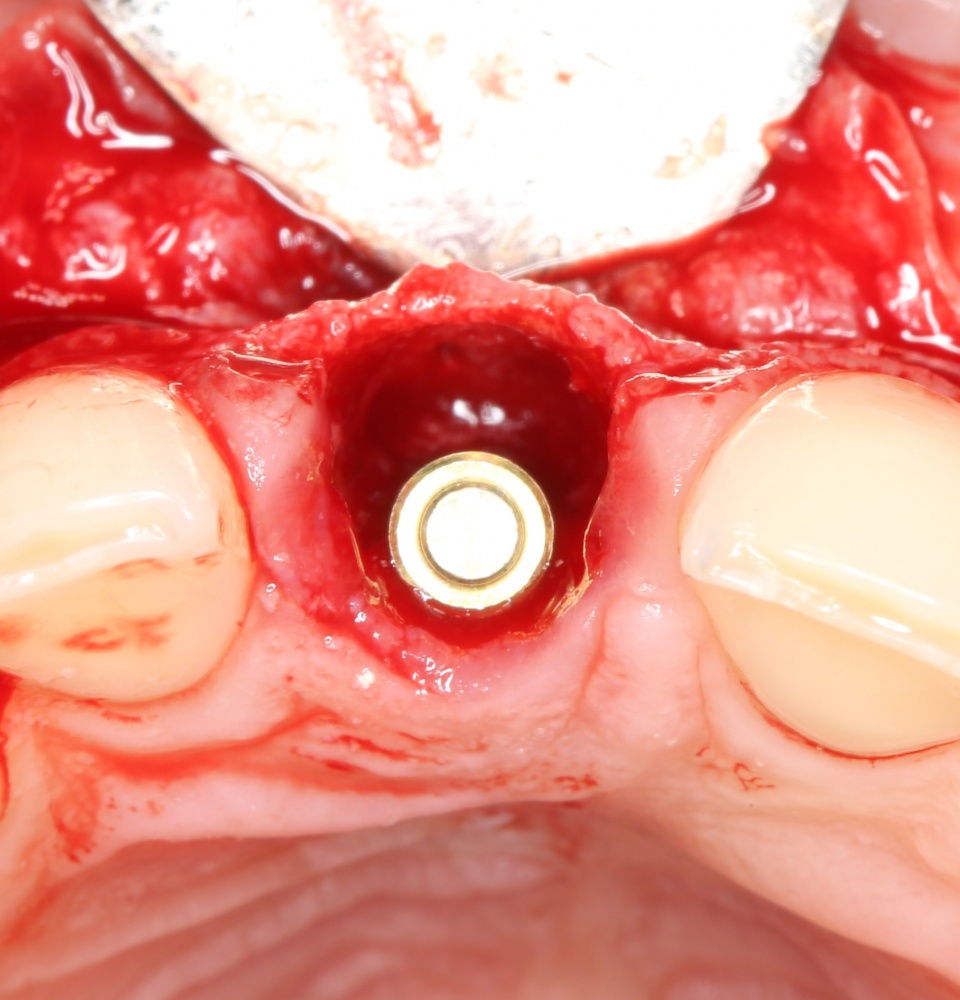

После удаления зуба и сопутствующей гранулемы, остается большая по размеру лунка с тонкой и поврежденной воспалительным процессом вестибулярной стенкой:

Первым делом, необходимо определиться с подготовкой лунки под имплантат. Проверить правильность позиционирования лунки можно с помощью аналогов имплантов, входящих в комплект XiVE Dentsply Implants:

Напомню, что при правильном позиционировании импланта в области фронтальных зубов, он прилегает к небной стенке лунки, а его ось выходит на небную поверхность будущей коронки. В крайнем случае, на режущий край.

Имплантат по объему всегда меньше, чем сам зуб:

Поэтому у нас возникает вопрос заполнения «пустого» пространства между вестибулярной стенкой лунки и поверхностью импланта. И, как ни странно, с Bio-Oss Collagen это удобнее сделать до установки имплантата.

Графт адаптируется (с помощью скальпеля), устанавливается в нужное положение. Для этого, опять же, очень удобно использовать аналоги имплантов из имплантологического набора (в крайнем случае, остеотомы или пины параллельности):